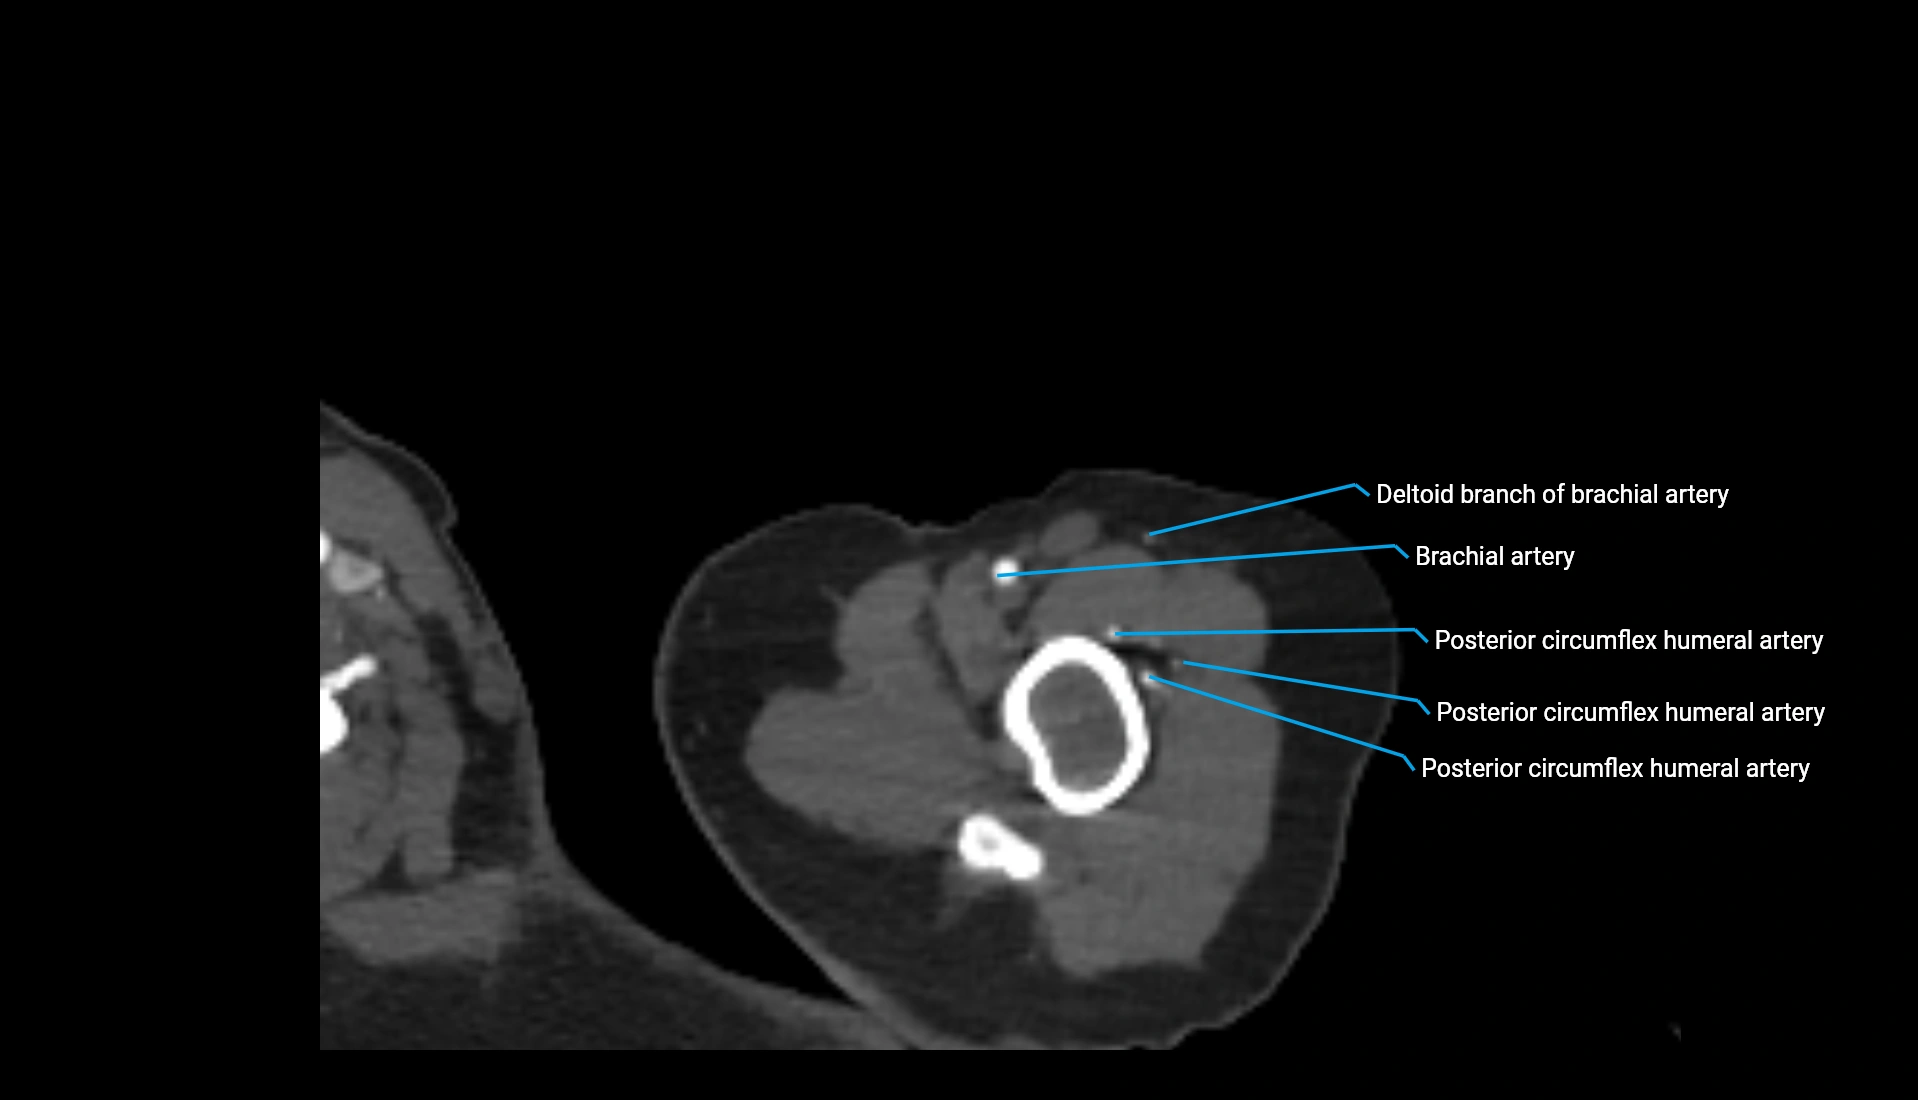

CT Appearance

Non-Contrast CT:

• Cortex: High-density, sharply defined

• Subchondral bone: Dense cancellous matrix

• Articular surface: Smooth concave contour articulating with the capitellum

• Excellent for evaluating bone integrity, alignment, and subtle fractures